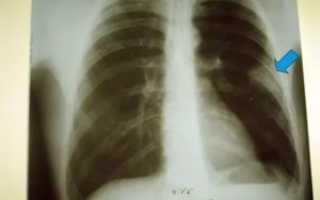

Достоверная визуальная диагностика плевральных шварт возможна только если соединительно-тканные образования больше 1 см в толщину. В противном случае тень от спаек накладывается на ткань легкого и не видна на рентгенограмме. При указании на характерные жалобы, которые возникли и сохраняются после перенесенного плеврита, требуется проведение дополнительных исследований таких, как:

Для обнаружения легочных заболеваний в первую очередь используется флюорография. Эту процедуру необходимо проводить ежегодно, в основном она направлена на выявление ранней стадии туберкулеза. Однако опытный рентгенолог может выявить на снимке образовавшиеся плевральные спайки, которые выглядят тенями. Причем форма их не меняется в зависимости от вдоха и выдоха.

При необходимости дополнительно назначается рентген. Как правило, спайки располагаются в нижней части легкого. При этом будет более темная картинка, а также может быть частичная деформация грудной клетки и диафрагмы.

Описание: левый купол диафрагмы подтянут плевральной спайкой. Легкие и сердце в норме.

На снимках тяжи выглядят затемненными участками легочного поля с усиленным сосудисто-соединительнотканным рисунком. При множественных поражениях определяются диффузные затемнения. Также возможно снижение высоты стояния ребер, уменьшение межреберного пространства и смещение органов.